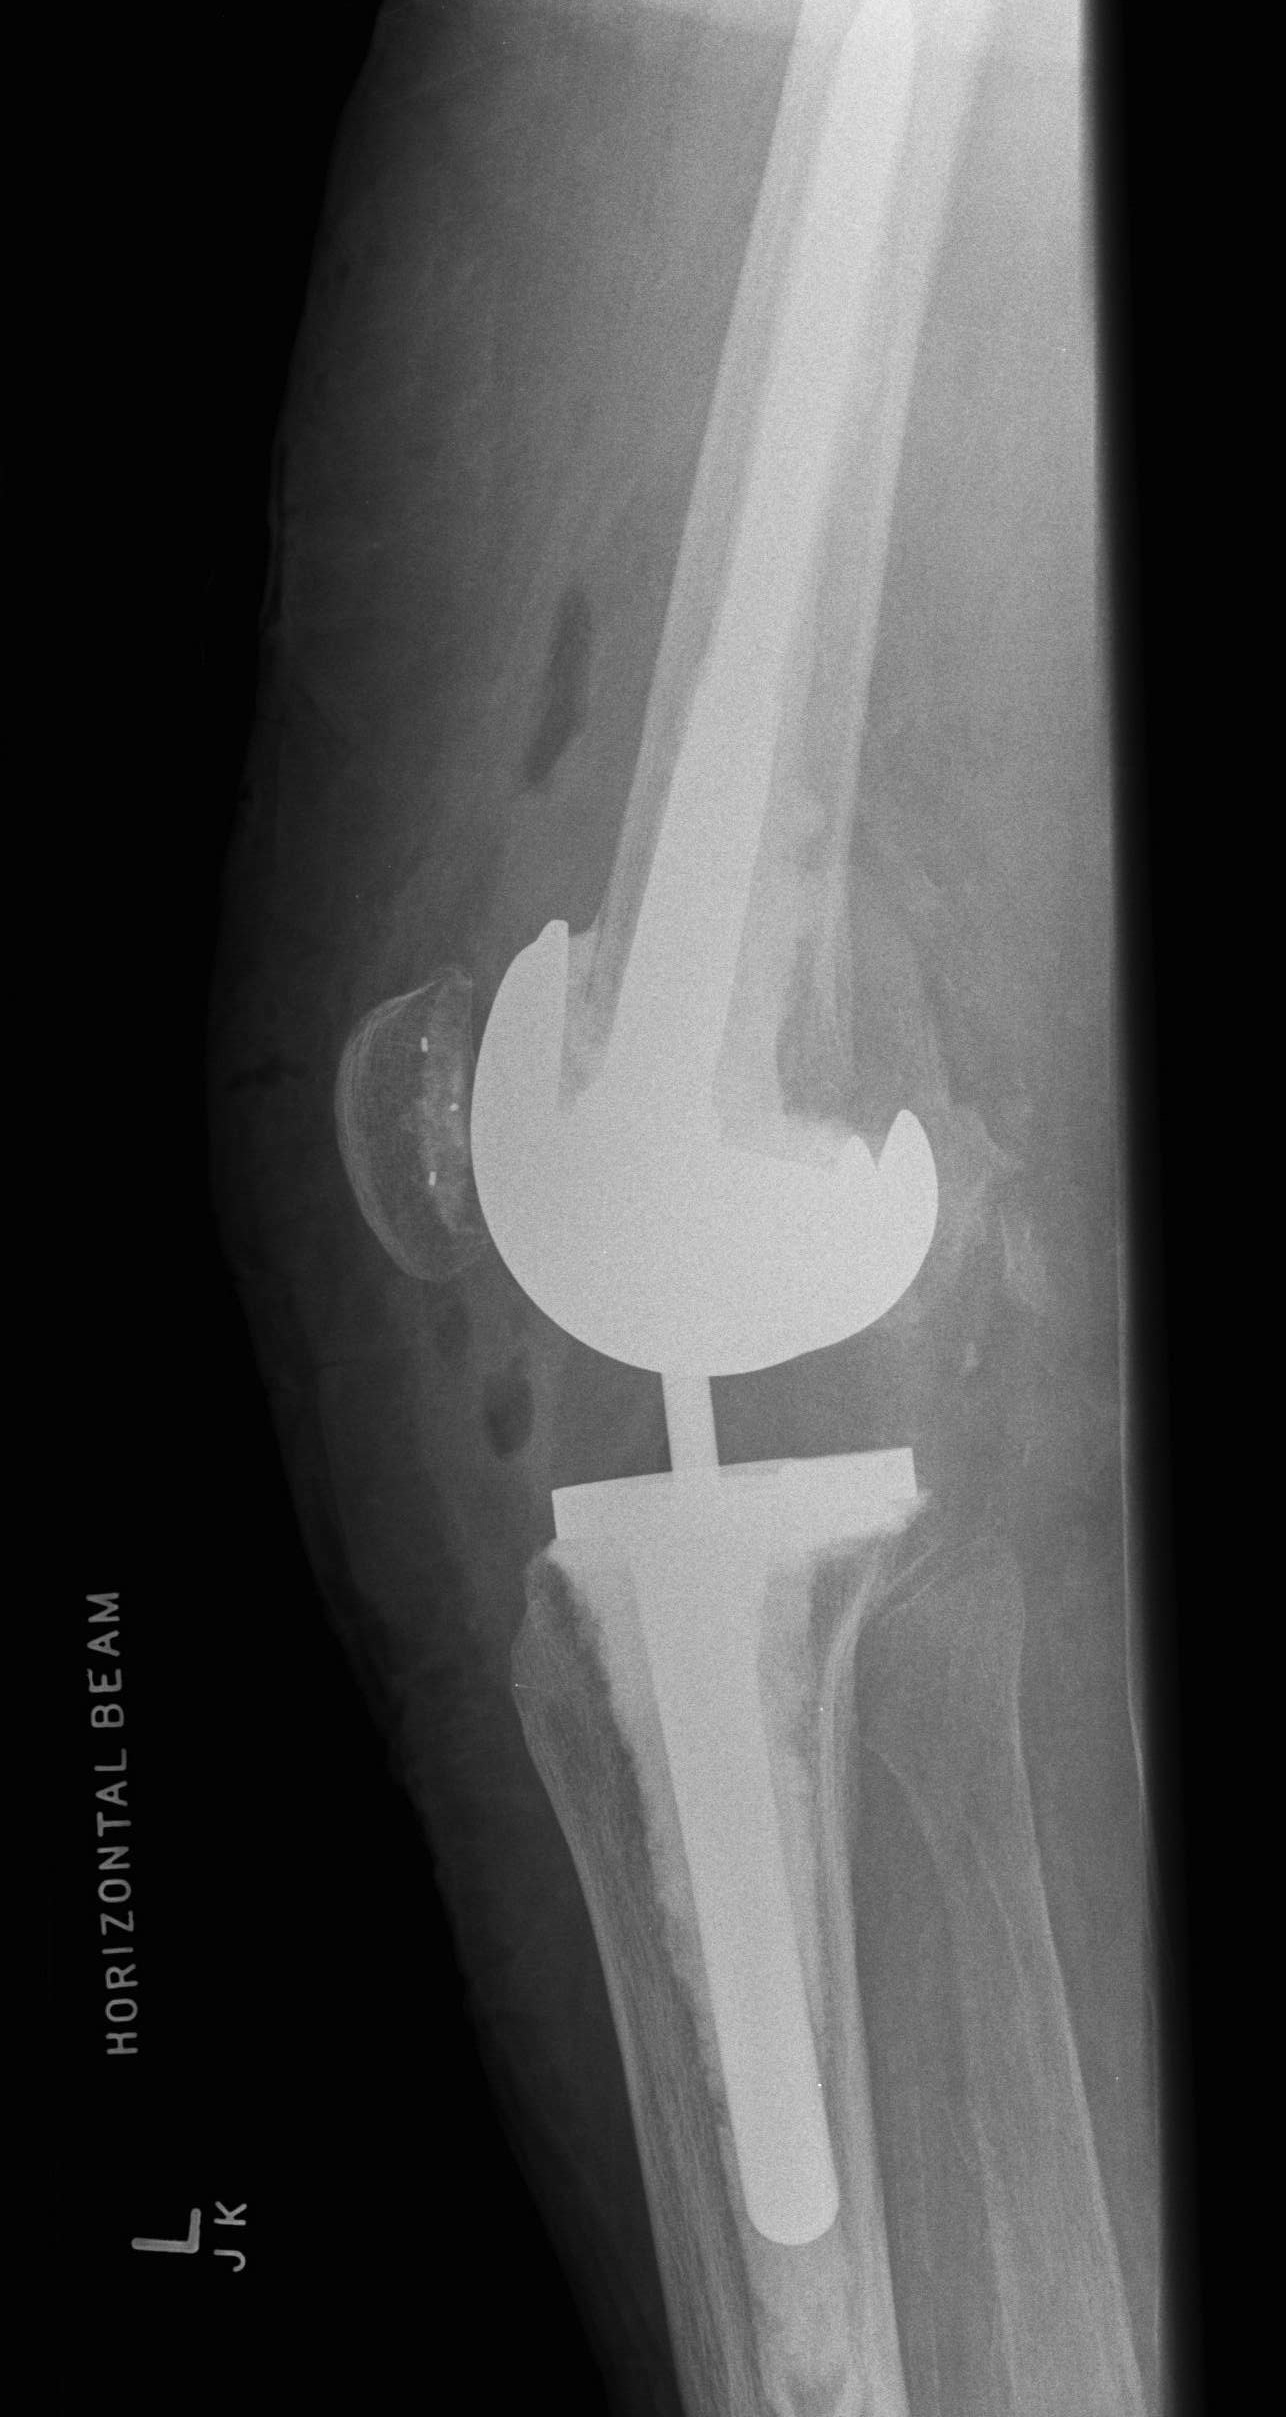

1. Reduce implant loosening

- offset load sharing to diaphysis

- 30% if > 70 mm

Indications

1. Using augments or bone grafting

2. Increased constraint

- VVS / hinge